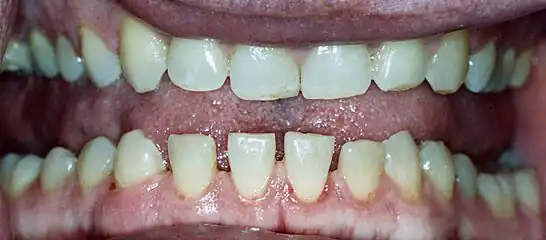

- Pronounced lower jaw protrusion (prognathism) with attendant macroglossia (enlargement of the tongue) and teeth spacing

Lower jaw showing the classic spacing of teeth due to acromegaly